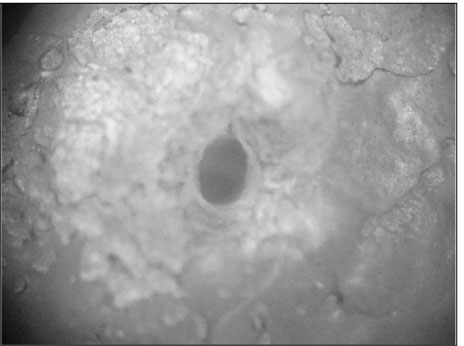

Figure 1

Photograph of the physiologic foramen of distal root (×60)

Figure 1 Photograph of the physiologic foramen of distal root (×60)